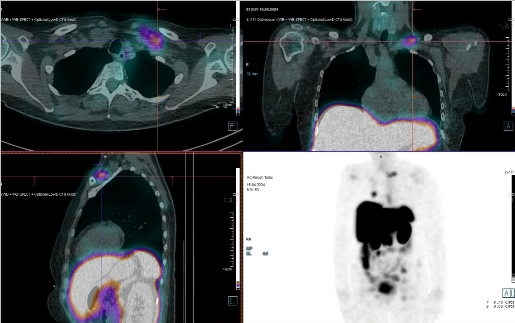

Scintigrafie Octreoscanem

I. v. jsme aplikovali 190 MBq analogu somatostatinu značeného 111In

(přípravek OctreoScan firmy Curium Netherlands B.V.) a provedli pomocí hybridní tomografické scintilační kamery Siemens Symbia Pro.specta X3 opatřené kolimátory pro střední energie planární celotělovou scintigrafii a cílenou tomografickou scintigrafii (SPECT) břicha a pánve kombinovanou s CT.

/ Obr. č. 3: Fúze SPECT/CT 4 hod. po aplikaci OctreoScanu. /

/ Obr. č. 4: Fúze SPECT/CT 4 hod. po aplikaci OctreoScanu. /

/ Obr. č. 5: Fúze SPECT/CT 4 hod. po aplikaci OctreoScanu. /

/ Obr. č. 6: Celotělová scintigrafie v přední a zadní projekci 24 hod. po aplikaci OctreoScanu.

/

Popis: pozorujeme patologická ložiska zvýšené depozice radiofarmaka-nově nekontrastně ve více LU v levém nadklíčku, v jedné parasternální LU vpravo (úroveň Th6) vel. 10 mm, v LU v dolním mediastinu prekardiálně cca 17 mm, tomograficky zachycena chabě zvýšená akumulace RF v Th páteři v úrovni obratlového těla Th7 a Th8 (v ldCT bez patologického korelátu, nově však v ldCT obraze zjištěna v. s. lýza pravého postranního výběžku obratle Th8), v levém jaterním laloku - S4b, v pravém jaterním laloku - S5 a S6, v LU paraaortálně v úrovni L2/3 15,5 mm - dnes okrsek nápadnější, chabě v levé kosti kyčelní dorsálně při SIS - částečná regrese od min. vyšetření.

Nález svědčí pro přítomnost vícečetných patologických ložisek zvýšené denzity somatostatinových receptorů ve výše uvedených lokalizacích. Ve srovnání s posledním vyšetřením jsou detekována nová ložiska v levém nadklíčku a mediastinu, susp. diskrétní nález i v Th páteři (obratel Th7 a Th8) se zachycenou lýzou postranního výběžku obratle Th8 vpravo v CT obraze, částečná regrese okrsku v levé kosti kyčelní oproti minulému vyšetření.

Závěr:

U nyní 70leté ženy s neuroendokrinním tumorem nejasného primárního zdroje prokazujeme progresi nálezu oproti vyšetření před 22 měsíci.